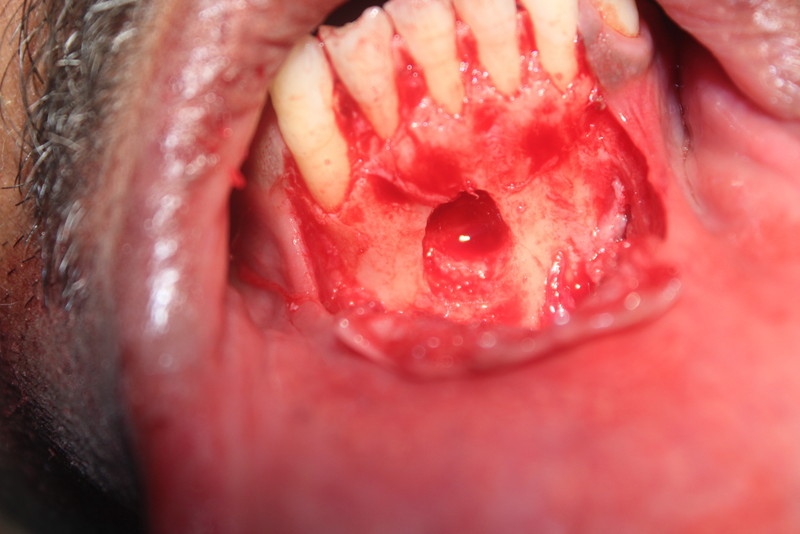

Dental Implants and Autogenous Bone Grafting